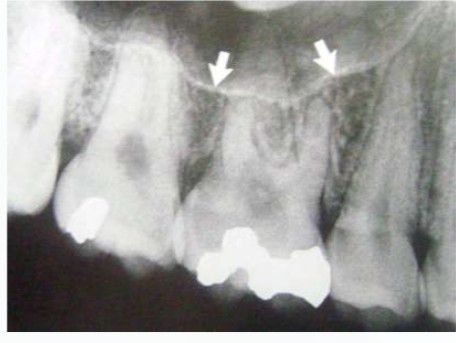

The maxillary sinus, or antrum of Highmore, lies within the body of the maxillary bone and is the largest and first to develop of the paranasal sinuses. The alveolar process of the maxilla supports the dentition and forms the inferior boundary of the sinus.